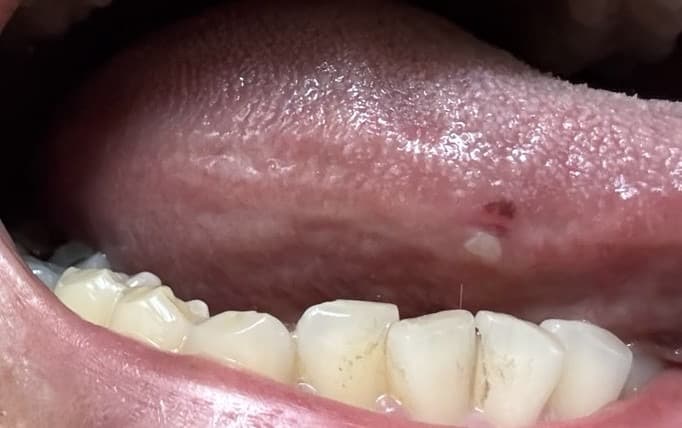

그리고 오늘 확인해보니까 두번째사진처럼

아직 하얗게 남아있는데

낫고있는건지 아니면 병원을 가봐야되는건지

혀에 생긴 문제로 걱정이 많으시겠네요. 사진으로만 봐서는 정확한 판단이 어렵지만, 하얗게 남아있는 것을 보면 염증 반응이거나 구강 건조로 인한 변화일 가능성이 있습니다. 혀는 예민한 부위라 작은 자극에도 쉽게 염증이 생길 수 있고, 수면 중 입안이 건조해지면 더욱 악화될 수 있어요.

사진을 보면 혀 점막에 외부 충격이 가해지면 일부 손상이 발생하였고 이후 염증 반응이 일어나면서 국소 설염이 발생한 것으로 보입니다. 이러한 설염은 특별한 치료 없이도 일반적으로 1-2주 이내에 호전이 되며 흡연자라면 흡연을 중단하는 것이 도움이 됩니다. 만약 1~2주 이후에도 호전이 없거나 궤양의 형태로 변한다면 이비인후과 진료를 보시는 것이 도움이 되니 고려해 보시기 바랍니다. 답변이 도움이 되었기를 바랍니다.